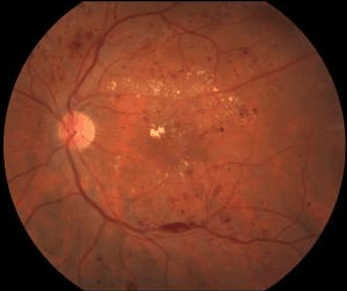

1. NPDR (non-proliferative diabetic retinopathy)

This is the early stage of diabetic retinopathy.

- Many people with diabetes have it but will not know about it because it does not cause vision problems until very late.

Leakage in the retina causing: blot and dot bleeding and leakage of fat. Vision may still be very good at this stage.